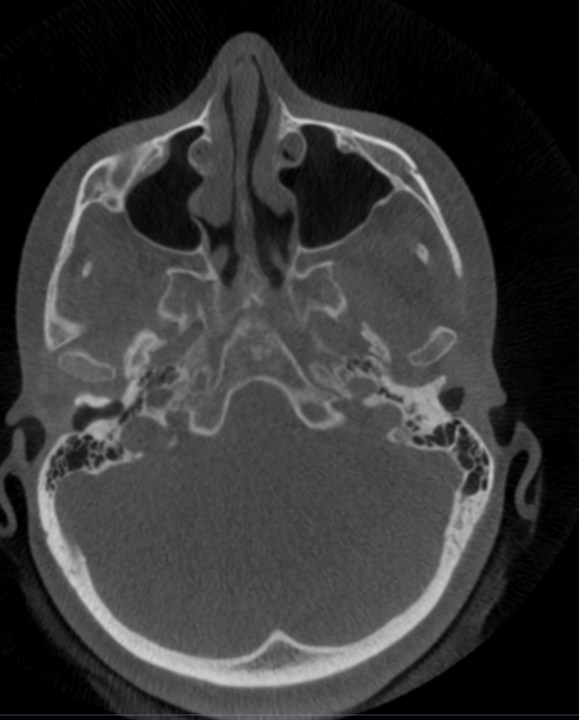

BENEFICIOS EN VÍAS AÉREAS

Aquí es donde el CBCT se vuelve oro puro para tu práctica:

- Evaluación volumétrica real

- Volumen total de vía aérea (mm³)

- Área mínima (zona crítica de colapso)

- Segmentación:

- Nasal

- Nasofaríngea

- Orofaringe

Esto te permite correlacionar con:

- Relación con postura y crecimiento

- Posición mandibular

- Colapso posterior de lengua

- Relación con columna cervical